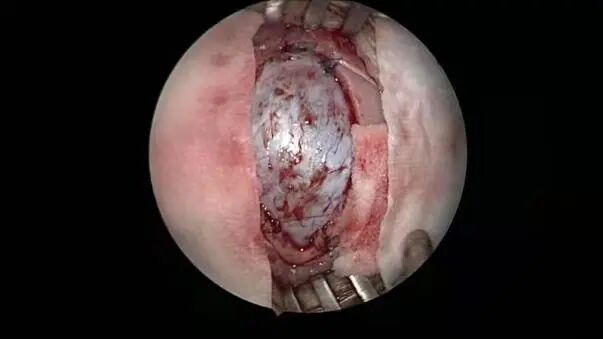

采用小骨窗進(jìn)行腦內(nèi)血腫清除術(shù)